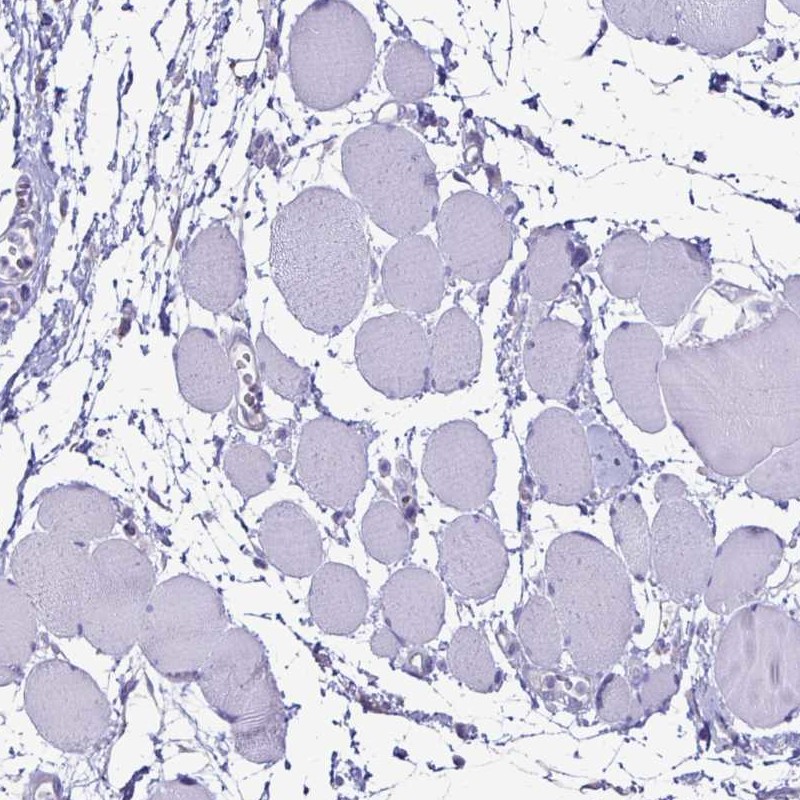

Immunohistochemistry analysis in human skin and skeletal muscle tissues using Anti-EVPL antibody. Corresponding EVPL RNA-seq data are presented for the same tissues.